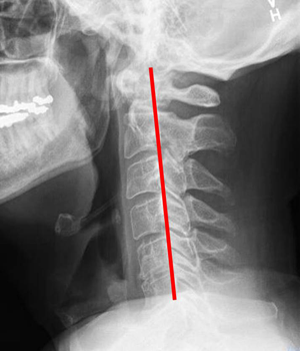

<ÀÏÀÚ¸ñȯÀÚ X-RAY / Á¤»ó ¸ñ X-RAY >

ÃÑ 33°³ÀÇ Ã´Ãß Áß °¡Àå À§¿¡ À§Ä¡ÇÑ °æÃß(¸ñ»À) 1¹øºÎÅÍ 7¹ø. Á¤»ó °æÃß´Â CÀÚ ÇüÅ·ΠµÇ¾î ÀÖÀ¸³ª ÀÏÀÚ º¯Çü µÇ¾î ÀÖ´Â »óŸ¦ ÀÏÀÚ¸ñ ÁõÈıºÀÌ¶ó ¸»ÇÏ¸ç ¸»¸ç ÈçÈ÷ °ÅºÏ¸ñ ÁõÈıºÀ̶ó°íµµ ÇÕ´Ï´Ù. º¸Åë ¿¬·É´ë°¡ ³ô°í ±ÙÀ°·®ÀÌ ºÎÁ·ÇÒ ¼ö·Ï ½±°Ô ¹ßº´ÇÏÁö¸¸ ÃÖ±Ùµé¾î ÄÄÇ»ÅÍ ¹× ¾É¾Æ¼­ ¾÷¹« ¹× »ýȰÀ» ¸¹ÀÌ Çϸ鼭 ¿¬·É, ¼ºº°¿¡ °ü°è¾øÀÌ ¹ß»ýºóµµ°¡ Áõ°¡Çϰí ÀÖ½À´Ï´Ù.